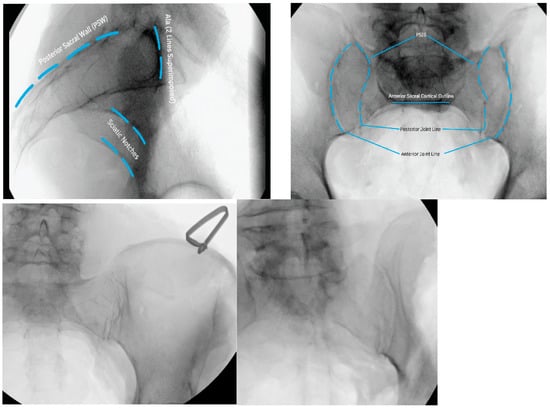

3.3.2. Intraoperative Imaging

3.3.3. Approach and Incision

3.3.4. Steinman Pin Placement